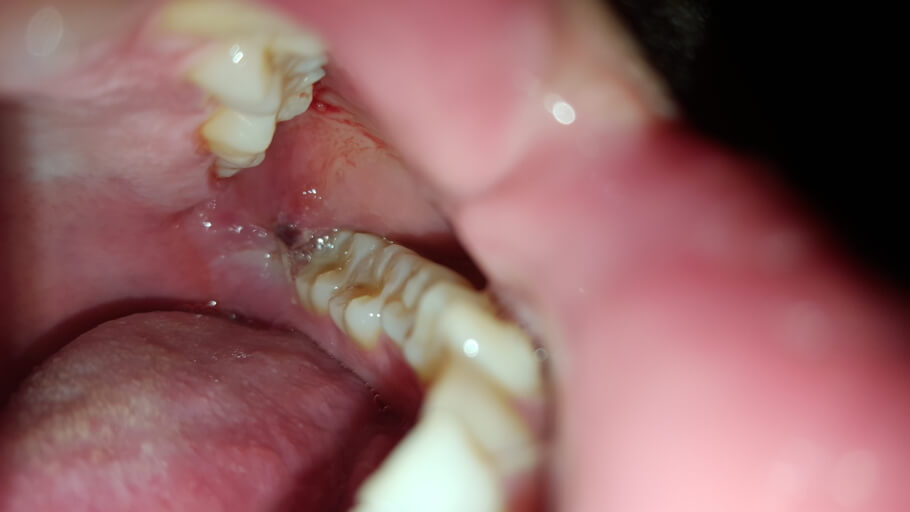

Hey there, I've recently taken out my wisdom tooth, (this is day 2) and took a picture of it. It was white, and im wondering if thats what it is supposed to look like. Lastly, there is a pimple-like structure to where the doctor injected the local anesthesia, is that normal? (PS I've attached a photo of what my inside mouth looks like atm, sorry if it's graphic.)

From the picture, everything looks like it is healing well. If you are not already, start rinsing with warm salt water 2-3 times daily. This is very therapeutic to the tissues and will help keep the area free from debris. The structure you are speaking of near the injection site is more than likely a salivary glad or an irritation from the injection. If it does not resolve on its own within the next 3-5 days, it would be a good idea to have the treating dentist re-examine the area.